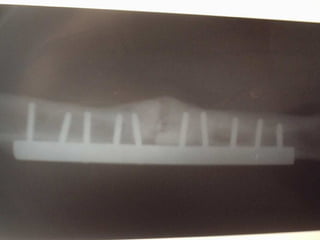

FIXAÇÃO INTERNA  (PLACAS,PARAFUSOS,HASTES, CERCLAGEM , FIOS DE KIRSCHNER) FIXAÇÃO EXTERNA ( FIXADORES EXTERNOS,ILIZAROV)